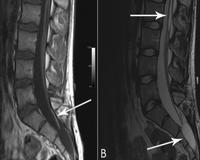

• МРТ спинного мозга. Исследование демонстрирует низкое положение и иммобилизацию конуса органа на дне утолщенной или укороченной конечной нити. Косвенные признаки включают незакрытие задней стенки позвоночного канала, нарушения сегментации позвонков, патологические образования в позвоночном канале.